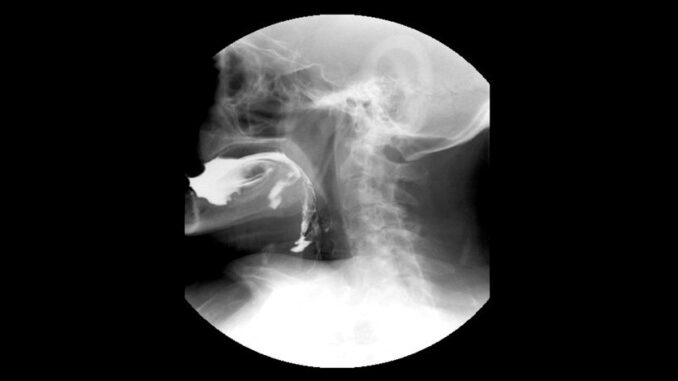

En el Hospital Materno Infantil de Tigre, el Municipio incorporó un nuevo estudio de videodeglución en el servicio de imágenes de rayos X para evaluar la deglución y advertir dificultades en la misma. Esta prestación médica amplía la capacidad de atención y mejora la recepción a niños y niñas.